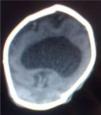

A su ingreso en la Unidad de alto riesgo neonatal, en regulares condiciones generales, presentaba los siguientes signos vitales: la frecuencia cardiaca era de 140 lpm y la respiratoria de 56rpm, con moderada palidez mucocutánea y microcefalia, con perímetro cefálico de 29cm; la fontanela anterior puntiforme depresible, microftalmia con hipotelorismo ocular, labio-paladar hendido amplio en todo su trayecto medial, micrognatia, los pabellones auriculares de implantación baja, el cuello es corto y pectus excavatum (fig. 1). La auscultación cardiopulmonar con soplo sistólico y murmullo vesicular rudo. En el abdomen cordón umbilical con arteria única y genitales de configuración normal. No se mostró alteración en las extremidades. El examen neurológico presentó reflejos primitivos. La ecografía transfontanelar no apreció línea media ni circunvoluciones cerebrales, ausencia de cuerpo calloso y septum pellucidum; los tálamos se encuentran fusionados y monoventrículo, compatible con holoprosencefalia alobar. El estudio de tomografía axial cerebral confirmó el diagnóstico (fig. 2). El estudio de ecocardiografía evidenció ducto arterioso persistente. El cariotipo en sangre periférica 46, XX/47,XX+13, metafases estudiadas 40, con 17,5% de células trisómicas.